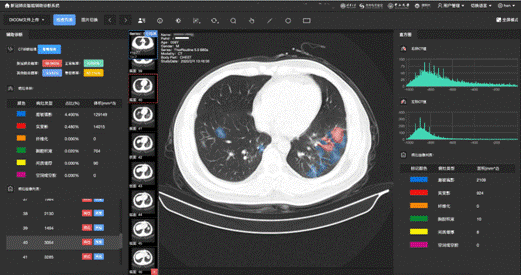

新冠肺炎影像辅助诊断应用界面

此外,通过医生手工标注的四千余张CT影像的典型病灶,系统可以对新冠肺炎、其他病毒性肺炎及细菌性肺炎的五类典型病灶(磨玻璃影、实变、空腔空洞等)自动进行精准定位,通过精准分析每一个病灶的大小和变化,可以作为药物筛选检测临床试验的判别标准。

在这项工作中,科研团队采用了总计53万多张的CT影像,构建了基于病灶分割的新冠肺炎智能诊断模型。该系统可对来自新冠肺炎患者、普通肺炎患者以及对照组的CT影像数据进行区分,诊断新冠肺炎的准确率达到了92.49%(灵敏度94.93%,特异度91.13%)。利用来自不同地区的不同数据集,这套AI诊断系统经受住了真实世界研究的考验——利用大规模的回溯性数据及前瞻队列研究,该AI系统均可达到90%左右的准确率,即便是使用海外的CT数据,这套系统也达到了84.11%的准确率。在回顾性数据中,系统获得了90.70%的准确率;在前瞻队列研究中,系统在一个疫情高发区获得了91.20%准确率,在两个疫情低发地区分别获得90.32%、89.67%的准确率。这一系列研究结果表明,这套AI诊断系统无论是采用中国数据还是国际数据,都具有良好的泛化性能。